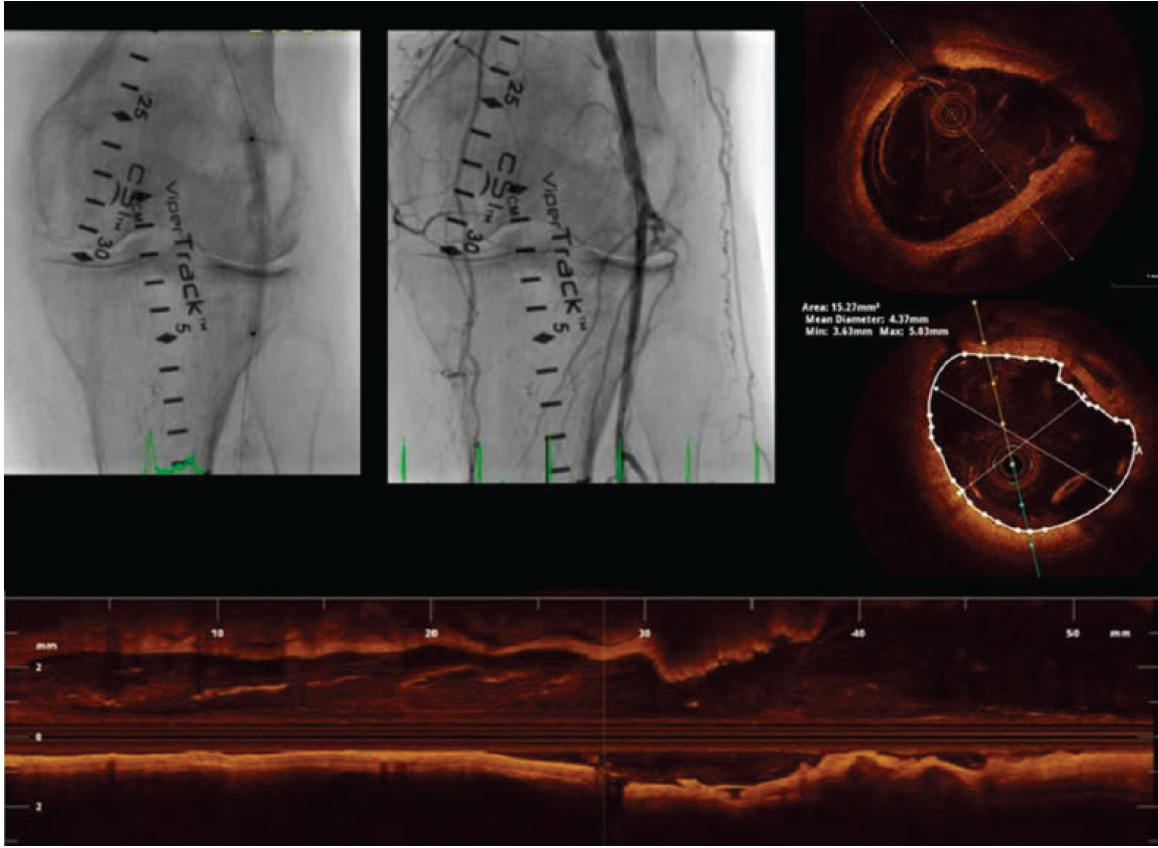

Case 3: Orbital Atherectomy and OCT-Guided Percutaneous Transluminal Angioplasty for Popliteal CTO

A 67-year-old gentleman with right lower extremity lifestyle-limiting claudication and abnormal ABI was referred to our institution for a right leg arterial angiogram and possible endovascular intervention. A 5 Fr sheath was placed in the left common femoral artery. A 5 Fr tennis racquet catheter was used for the abdominal aortogram and a 5 Fr internal

mammary (IM) catheter for the selective right femoral angiogram after left-to-right crossover. A chronic, subtotally occluded right distal popliteal stenosis extending to the tibioperoneal trunk was identified and we elected to go ahead with a endovascular recanalization approach. The 5 Fr sheath was exchanged for a 6 Fr, 45 cm long sheath. A 300 cm, .014-inch Regalia guidewire (Asahi Intecc) was advanced to the right posterior tibial artery and a baseline OCT was performed (Figure 6). Due to significant calcification identified with OCT, we decided to perform an

orbital atherectomy recanalization using the Diamondback 360 atherectomy device (Cardiovascular Systems, Inc.) in the affected segment. Although atherectomy established excellent angiographic flow, due to mild angiographic “haziness” at the site of intervention, we elected to perform a follow-up OCT (Figure 7). OCT demonstrated multiple segments of endothelial protrusion in the arterial lumen. Although data regarding the clinical significance of such OCT findings is currently absent, we decided to proceed with a 3.5 mm × 100 mm × 150 mm Sterling balloon (Boston Scientific) angioplasty. Final angiographic and OCT imaging showed good results (Figure 8).